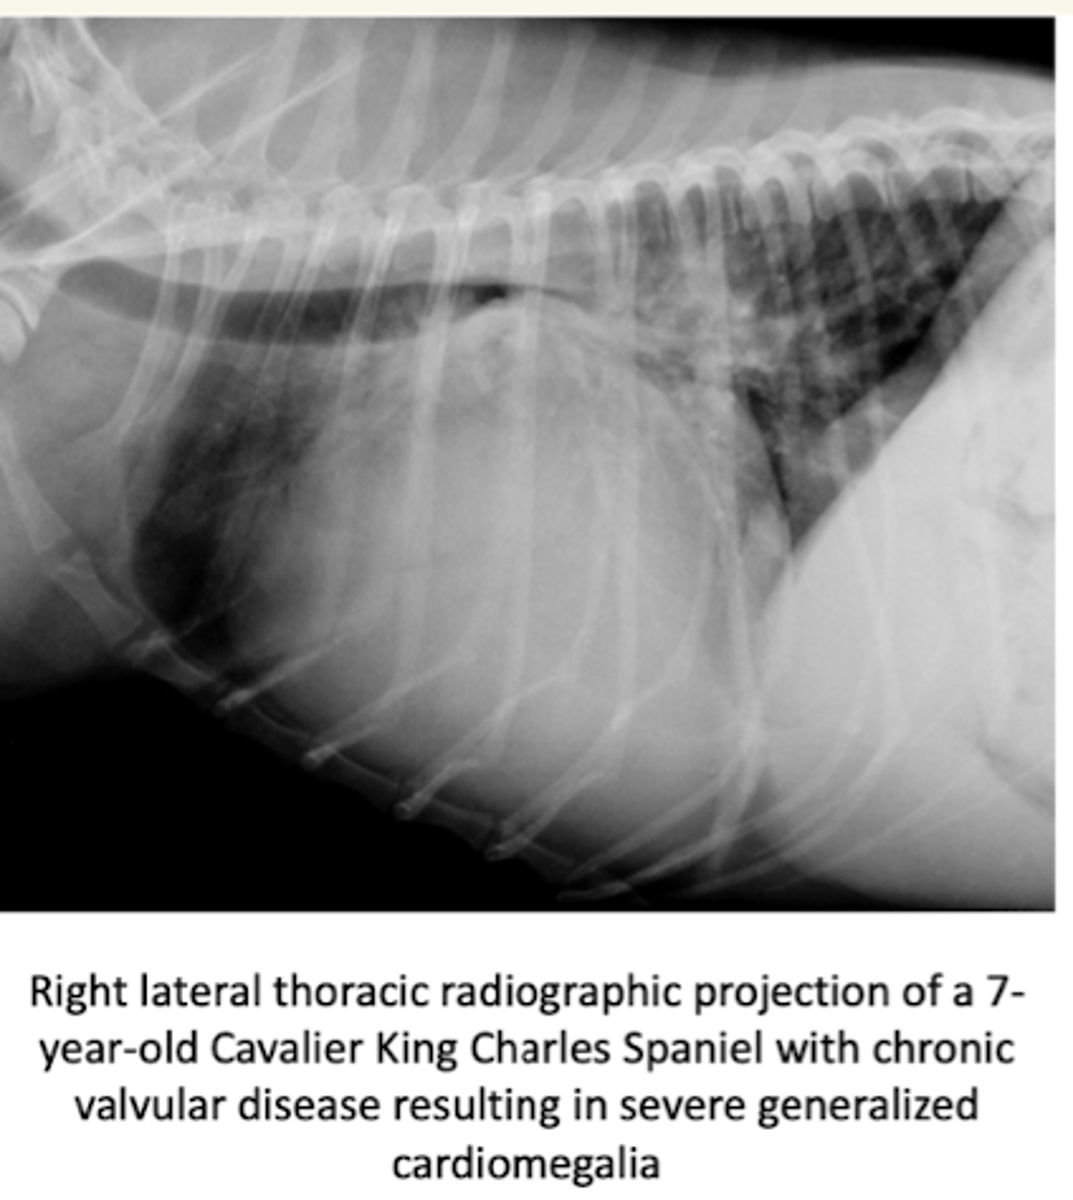

¿cuales alteraciones cardiacas se puede ver con una radiografía torácica?

- distensión venosa pulmonar

- edema pulmonar intersticial

- cambios en la silueta cardiaca: hipertrofia/ dilatación